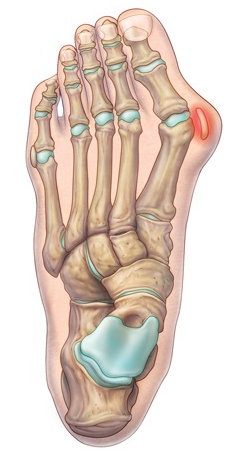

• Na avaliação radiográfica em AP com carga, quais os principais ângulos a serem traçados?

A

• Ângulo de valgismo do hálux (metatarsofalângico)

• Ângulo intermetatarsal

• Ângulo de valgismo interfalângico do hálux

• Ângulo articular metatarsal distal (AAMD)

• Na radiografia em AP com carga, como é traçado o ângulo intermetatarsal?

• Ângulo entre o eixo longo do 1° e do 2° raio

• Normal → até 9°

• Leve → 9° a 12°

• Moderado → 13° a 15°

• Grave → > 16°

• Na radiografia em AP com carga, como é traçado o ângulo de valgismo do hálux (metatarsofalângico)?

• Ângulo entre o eixo longo do 1° mtt e o eixo longo da falange proximal

• Normal → até 15°

• Leve → < 25°

• Moderado → 25° a 40°

• Grave → > 40°